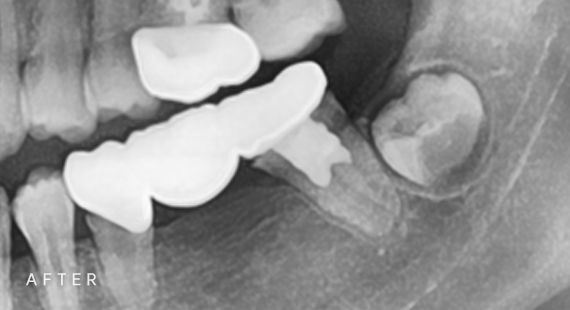

임플란트